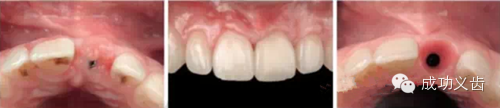

图3.即刻种植1,2008年的拔牙即刻种植病例,完美修复效果。

图4.即刻种植2,2013年复查。种植体周围骨组织稳定,龈乳头依然尖锐。颜色粉嫩,赏心悦目。